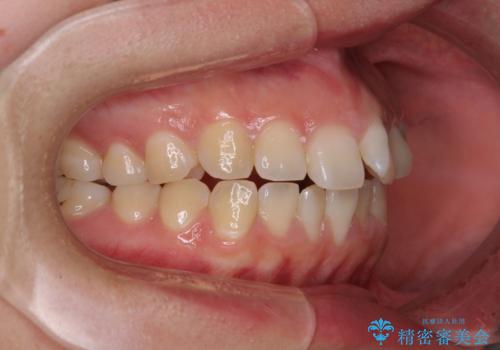

- 上下の前歯が非接触であることと、それに伴う口元の閉じにくさを気にして来院された患者様です。

奥歯の咬み合わせを見ると、上顎が下顎に対して相対的に前方にありました。

口元の閉じにくさを改善するためには、上顎臼歯を後方に移動させた咬み合わせにする必要があります。

インビザライン単体で改善することも可能ですが、達成する可能性が高くないため、カリエールディスタライザーという補助装置を併用して、より確実性を上げることとしました。

奥歯の咬み合わせを改善しながら、並行してインビザラインで歯列を整えることとしました。

カリエールディスタライザーを併用したことで、確実かつ短期間で治療を終えることができました。